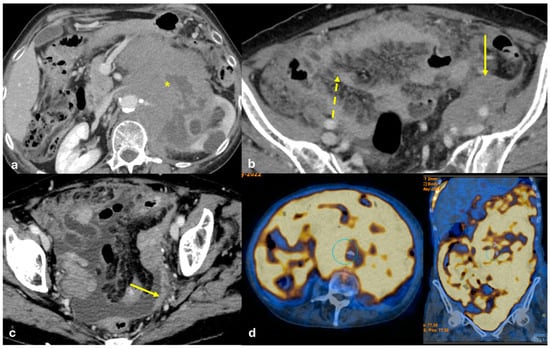

- Plaque pattern: confluent nodular plaques, typically involving the lower surface of the right diaphragm (Figure 3);